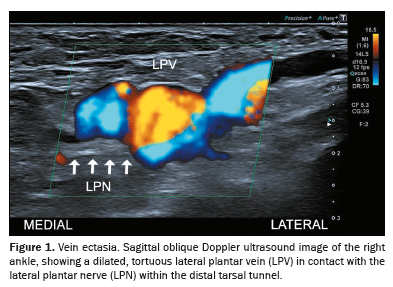

Thrombosis

Thrombosis (Figure 3), leading to the expansion of veins, is also a known factor in the development of TTS. Such vascular changes bring the veins into direct contact with the tibial or plantar nerve, potentially causing compression and related symptoms(1,7).